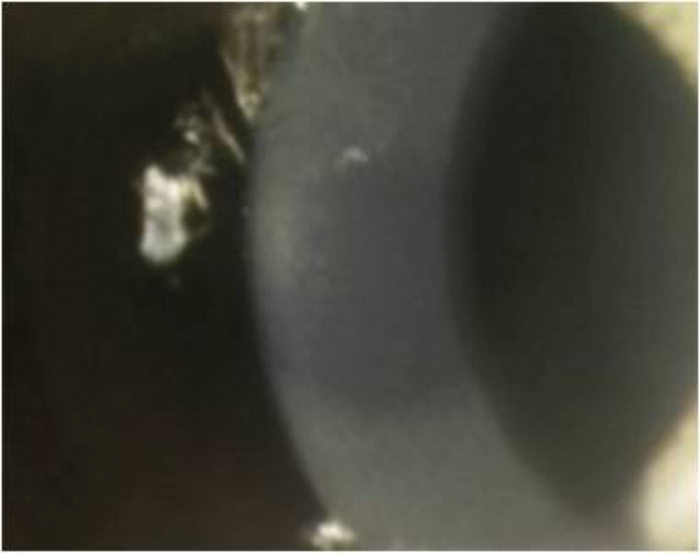

Figure 2a: Annular pattern of diffuse lamellar keratitis on day one after surgery.

Figure 2b: Central toxic keratopathy (CTK) presenting on day six after surgery.

Figure 2c: The same case after resolution of the CTK at one year after surgery.

An annular pattern of DLK seen on Day 1 can be a prelude to central toxic keratopathy. This syndrome presents with focal opacification and thinning of the stromal bed with ‘mud crack’ interfacial striae, typically on day four to seven after surgery. The aetiology of CTK remains unclear, but it occurs in the context of interface inflammation, and anything other than mild, diffuse DLK should be washed out at the interface with BSS on day one. Treatment of CTK is conservative, with no flap lift, and cessation of topical steroids after resolution of the associated interface inflammation [4]. Confocal microscopy shows keratocyte apoptosis back to Descemets membrane at the site of the opacity in CTK, with repopulation and at least partial resolution of the initial irregular hyperopic shift between three and 12 months after onset. There are no reports of recurrent CTK, and enhancement treatment once the refraction has stabilised can be performed if necessary.